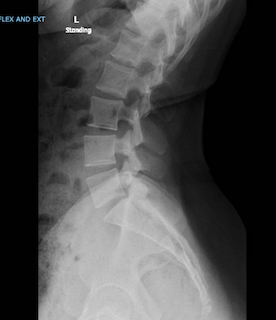

Lateral X-ray of the cervical spine showing vertebrae, intervertebral discs, and spinal alignment.

X-rays are often helpful even if an MRI has already been performed, as they provide important information about alignment and spinal stability.

• If you have not previously had X-rays of your spine, our office will usually obtain X-rays prior to your visit so they can be reviewed during your consultation.